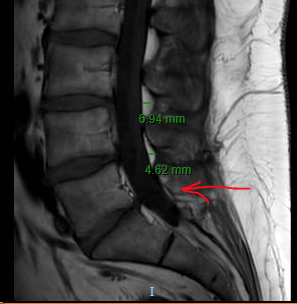

Regarding epidural space at different levels. I have noticed over the years that there doesn't seem to be much space (but i'm sure there is plenty of potential space) at L5 - at least while the person is lying supine in an MRI scanner.

Here are two random l-spine MRIs on the scanner from today, T1 IMAGES to highlight the fat so epidural space is well visualized. This pattern is very reproducible.

PATIENT #1

Very interesting observations and images of L5-S1. Thanks for posting.

I do find myself often at L5-S1 for ILESI as it lures you in with that wide open interlaminar window. I often can’t see any interlaminar space at L4-5 because of all of the pathology commonly there. However; perhaps because of the smaller epidural space and thin LF, I see a lot of mixed epidural and intradural spread of contrast.